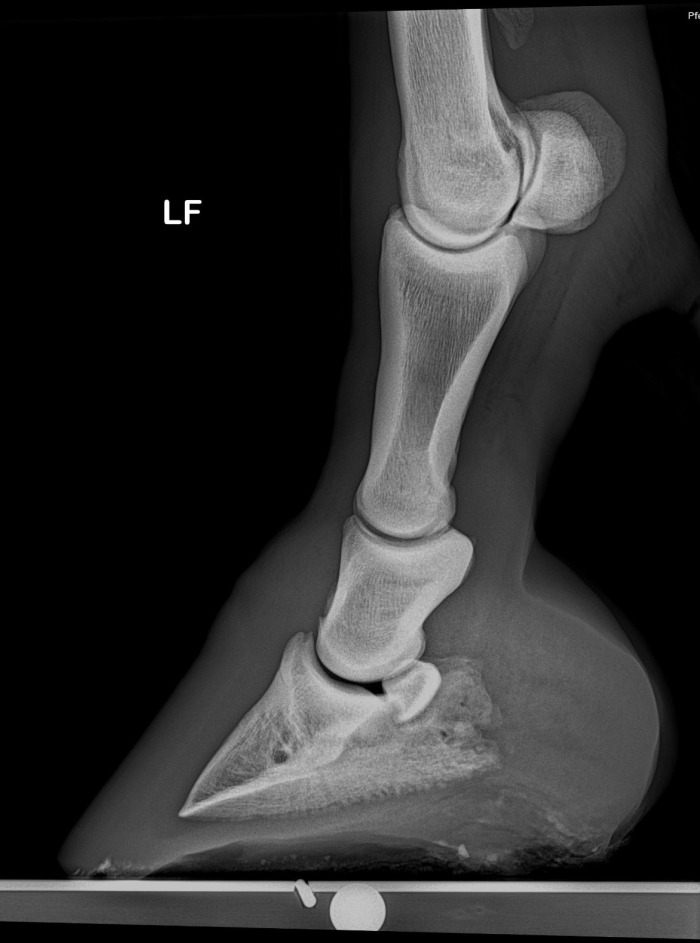

• Anatomie des Hufes – wie ist der Huf aufgebaut?

• Wie sieht ein gesunder, physiologischer Huf aus?

• Wie und weshalb entstehen Hufprobleme?

• Woran erkennt man einen deformierten Huf?